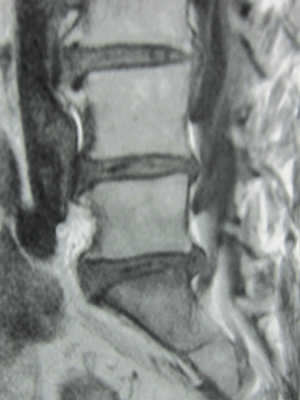

• 椎間板ヘルニア

腰は5個の椎骨からなりますが椎骨と椎骨の間にクッションの役割を果たす[椎間板]があります。

その椎間板は線維輪と髄核で構成されていますが、その髄核が線維輪を破って飛び出した状態が椎間板ヘルニアです。

その症状は腰痛と下肢痛です。

両方の症状をおこすことも多いのですが、腰痛または下肢痛のみという場合もあります。